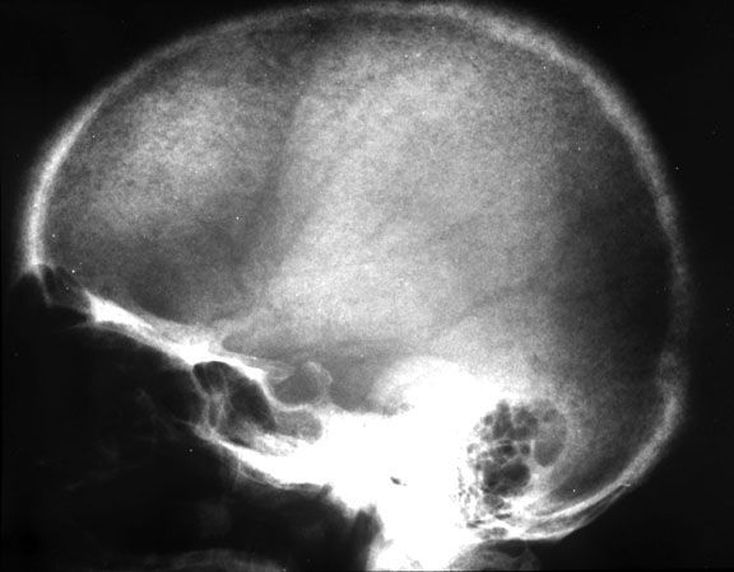

Parathyroid hormone is the main hormone that maintains a balance of calcium and phosphate in our bodies. When released, parathyroid hormone increases the release of calcium from the bone, reabsorption from the kidney, and secondarily stimulates absorption of calcium from the intestines. It also stimulates secretion of phosphate in the kidney. Hyperparathyroidism is the abnormal secretion of parathyroid hormone. Clinical findings: The classic medical school clinical findings are "Stones, Bones, abdominal moans, and psychiatric overtones," referring to renal calculi, bone pain, peptic ulcers, pancreatitis, and CNS symptoms (confusion lethargy, weakness). Depending on the etiology, the serum calcium may be elevated and phosphate may be decreased. Etiology: Primary Hyperparathyroidism Excessive parathyroid hormone due to a parathyroid gland abnormality 80% parathyroid adenoma 12% parathyroid hyperplasia (rarely from Multiple endocrine neoplasia) 1-3% parathyroid carcinoma Secondary Hyperparathyroidism Excessive parathyroid hormone due to an abnormality elsewhere in the body. Most often this is from chronic renal failure where elevated phosphate and +/- decreased calcium lead to chronic stimulation of the parathyroid gland. Tertiary Hyperparathyroidism Excessive parathyroid hormone due to autonomous secretion of parathyroid hormone. Often this is from prolonged secondary hyperparathyroidism from renal failure. Then, when the patient receives a renal transplant, cause of the secondary hyperparathyroidism is taken away, but the parathyroid glands continue to over secrete parathyroid hormone. Skull shows granular decalcification giving appearance of salt and pepper.